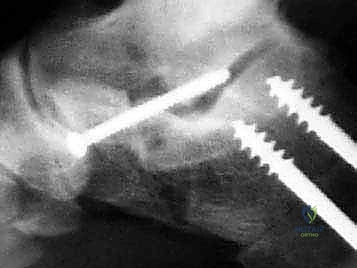

إطالة العمود الجانبي للقدم، أو قطع عظم إيفانز، هو إجراء جراحي حيوي لتصحيح تشوه القدم المسطحة المكتسبة الناتج عن قصور الوتر الظنبوبي الخلفي. يهدف إلى استعادة قوس القدم وتخفيف الألم وتحسين وظيفة القدم، ويتم على يد خبراء مثل الأستاذ الدكتور محمد هطيف.

في هذا الدليل المرجعي، سنسلط الضوء بشكل مكثف على الحل الجراحي المتقدم والفعال المعروف باسم إطالة العمود الجانبي للقدم (Lateral Column Lengthening)، وتحديداً التقنية الجراحية الدقيقة المسماة "قطع عظم إيفانز" (Evans Osteotomy). يُعد هذا الإجراء حجر الزاوية في استعادة الميكانيكا الحيوية الطبيعية للقدم، وإعادة بناء القوس المنهار، وتخفيف الألم بشكل دائم.

* الأشعة السينية (X-rays) مع تحمل الوزن: ضرورية لتقييم درجة انهيار القوس وزوايا العظام (مثل زاوية تالونافيكولار Meary's Angle).